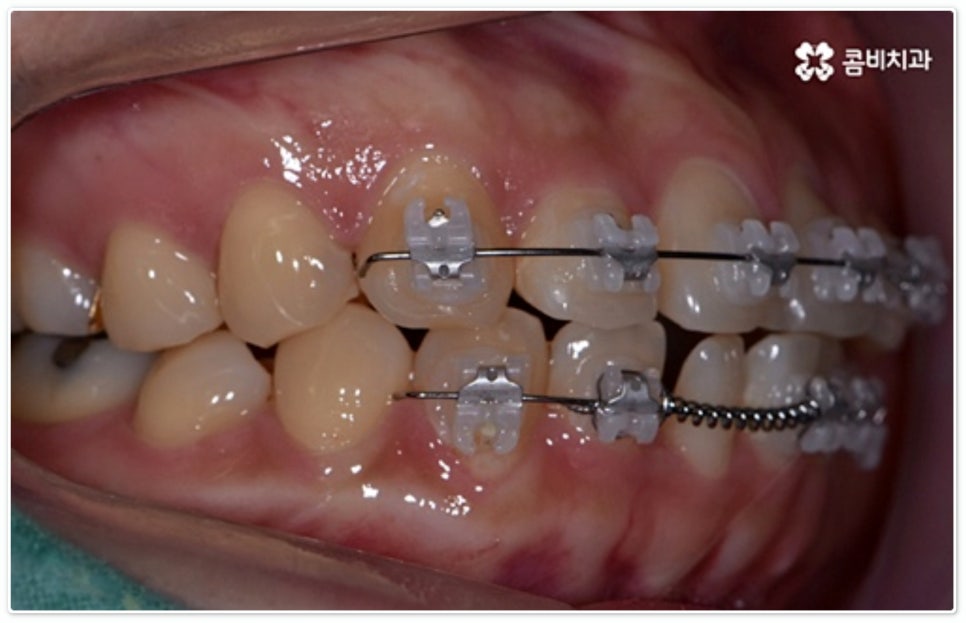

그렇지 않고 전후방 각도 조절 또는 단순 횡적인 움직임으로 치열 개선이 가능한 케이스는 부분 교정을 진행하는데, 사진에서 보시는 사례가 바로 그런 경우에 속하고 있습니다. 앞니 6개에만 브라켓을 부착하였는데 보시다시피 치아 색상과 유사한 세라믹 재질의 장치를 이용하여 심미성 또한 높여 주었음을 알 수 있어요.